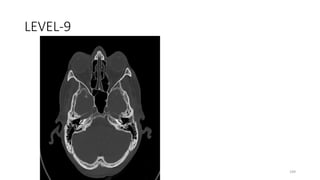

LEVEL-9

199

BASAL TURN OF COCHLEA

200

Groove in body of sphenoid bone for internal

carotid artery

201

MIDDLE EAR

202

SQUOMOS OCCIPUT

203

OCCIPITO MASTOID SUTURE

204

Space connecting superior and inferior orbital

fissures

205

BODY SPHENOID

206

GREATER WING SPHENOID

207

SPHENO SQUAMOUS SUTURE

208

SPHENO ZYGOMATIC SUTURE

209

TEMPORAL BONE, SQUAMOUS PART

210